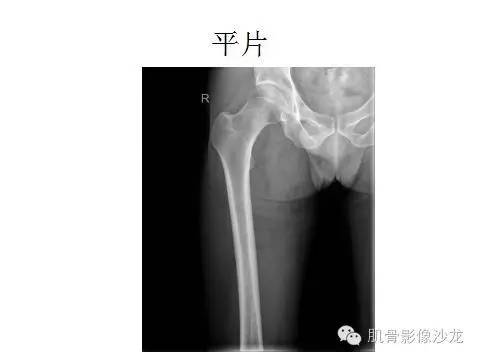

先看平片 老师们有什么发现

股骨头下

囊状病灶

我感觉是颈不太对

耻骨支有破坏?周围软组织肿块

有点周围花环样强化 软骨肉瘤可以考虑 但是平片一点钙化没见到